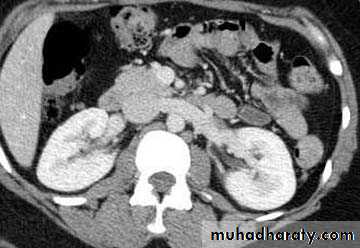

CT scanContrast enhanced CT scan through the kidneys in nephrogram phase 90-100 seconds following contrast administration and would show renal lesions well.

Contrast enhanced CT scan through the kidneys in pyelogram phase (showing excretion of contrast into the collecting system). This is approximately 10-15 minutes following contrast administration and would show urothelial lesions well, such as transitional cell carcinoma, stones, blood clots.